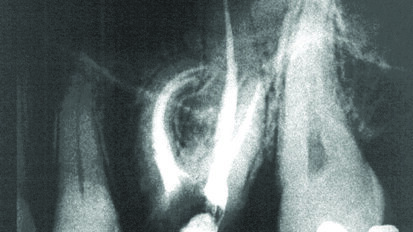

Lepljenje fragmenta i nadogradnja frakturiranog maksilarnog centralnog sekutića

Akutna dentalna trauma je veoma česta među decom mlađom od 12 godina. Najčešće povređivani zubi su maksilarni sekutići, a prilikom traume ...